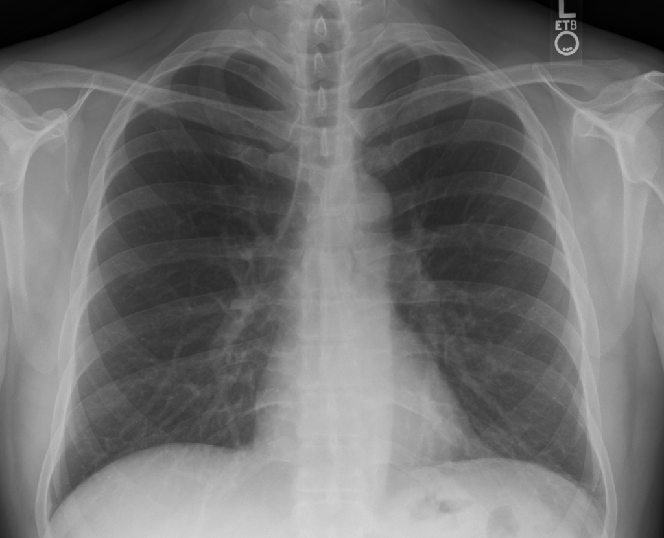

Cardiomegaly Chest Xray

Heart Rentgen Citation, doi, disclosures and article data. From the right to the left. Congestive heart failure (chf) is the result of insufficient output because of cardiac failure, high resistance in the circulation or fluid overload. The cardiac anatomy will be discussed in the order of normal blood flow: Left ventricular enlargement can be the result of a number of. Last revised by yuranga weerakkody on 4 sep 2021. Citation, doi, disclosures and article data.